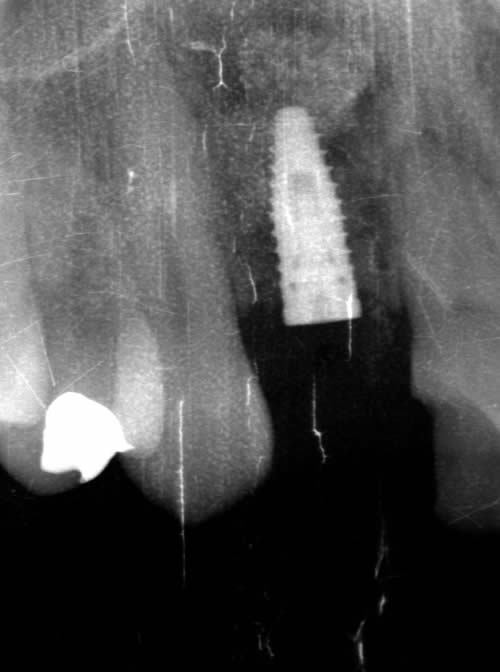

< 症例1 >

- 治療期間:6ヶ月

- 治療回数:8回

- 治療歯数:1歯

- 費用:インプラント治療:45万円 上部セラミック:89,000円

- リスク:メンテナンスを怠ると、インプラント周囲炎になる可能性があります。

- インプラント手術には合併症が伴う場合があります。

- 治療期間は治癒の状態により前後する場合があります。